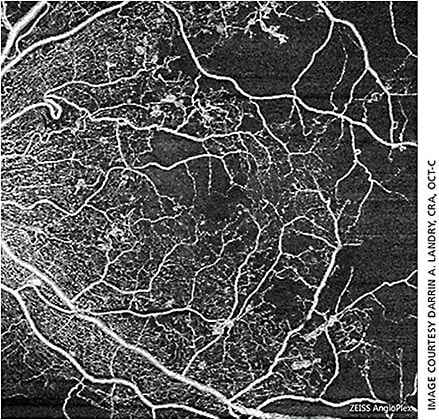

Because the particles moving in blood cause the most variation in the phase and intensity of backscattered light, blood vessels appear brightest on OCTA images and static tissue (retinal structures, nonmoving structures) appear dark. The resulting image closely mimics an early fluorescein angiogram, as vascularity is illustrated in white (or false color — pseudo color is applied to the image to illustrate the different depths of vasculature) (Figures 1 and 2). The important difference between OCT and OCTA: OCT images anatomical structure, while OCTA images vascular structure.1

OCTA utilizes OCT technology, which scans in the X and Y axes. OCTA also scans in the Z axis, allowing for imaging “en face,” which is similar to how we image posterior pole color and dye angiography. Using en-face imaging, the OCTA images multiple layers from the anterior retina to the choroid (Figure 3).1